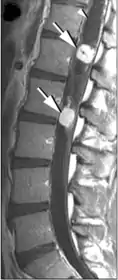

Гемангиобластомы в области позвоночного канала обычно располагаются интрамедуллярно (в спинном мозге), но могут находиться и экстрамедуллярно (вне спинного мозга). В 50 % они поражают грудной отдел и в 40 % шейный. Так как гемангиобластомы представляют собой богатоваскуляризированные новообразования, то их клиническая манифестация может дебютировать субарахноидальным кровоизлиянием[12][26].

В большинстве случаев гемангиобластомы в области позвоночного канала представляют собой солитарное образование, однако в 20 % могут наблюдаться множественные новообразования (как правило, при болезни Гиппеля — Линдау). Приблизительно в половине случаев (43—60 %) образуются сирингомиелические полости. Кисты могут достигать больших размеров, располагаясь выше и ниже солидного узла опухоли[26][27][28].

Компьютерная томография с контрастным усилением позволяет хорошо визуализировать гемангиобластому. На МР томограммах узел опухоли имеет гипо- или изоинтенсивный сигнал на Т1-взвешенных томограммах и гиперинтенсивный — на Т2-взвешенных. Кистозные полости имеют сигнал, близкий по своим характеристикам к ликвору. Узел опухоли хорошо накапливает контрастные вещества. При этом интенсивность сигнала от стенок кист обычно не повышается[26][28].

Хотя гемангиобластомы на магнитно-резонансных томограммах и не имеют признаков, которые с полной достоверностью свидетельствовали бы именно о наличии данного новообразования, можно выделить несколько характерных признаков[26]:

- сочетание больших кистозных образований с небольшим солидным узлом;

- наличие расширенных и извитых сосудов в субарахноидальном пространстве спинного мозга;

- множественность поражения при болезни Гиппеля — Линдау.